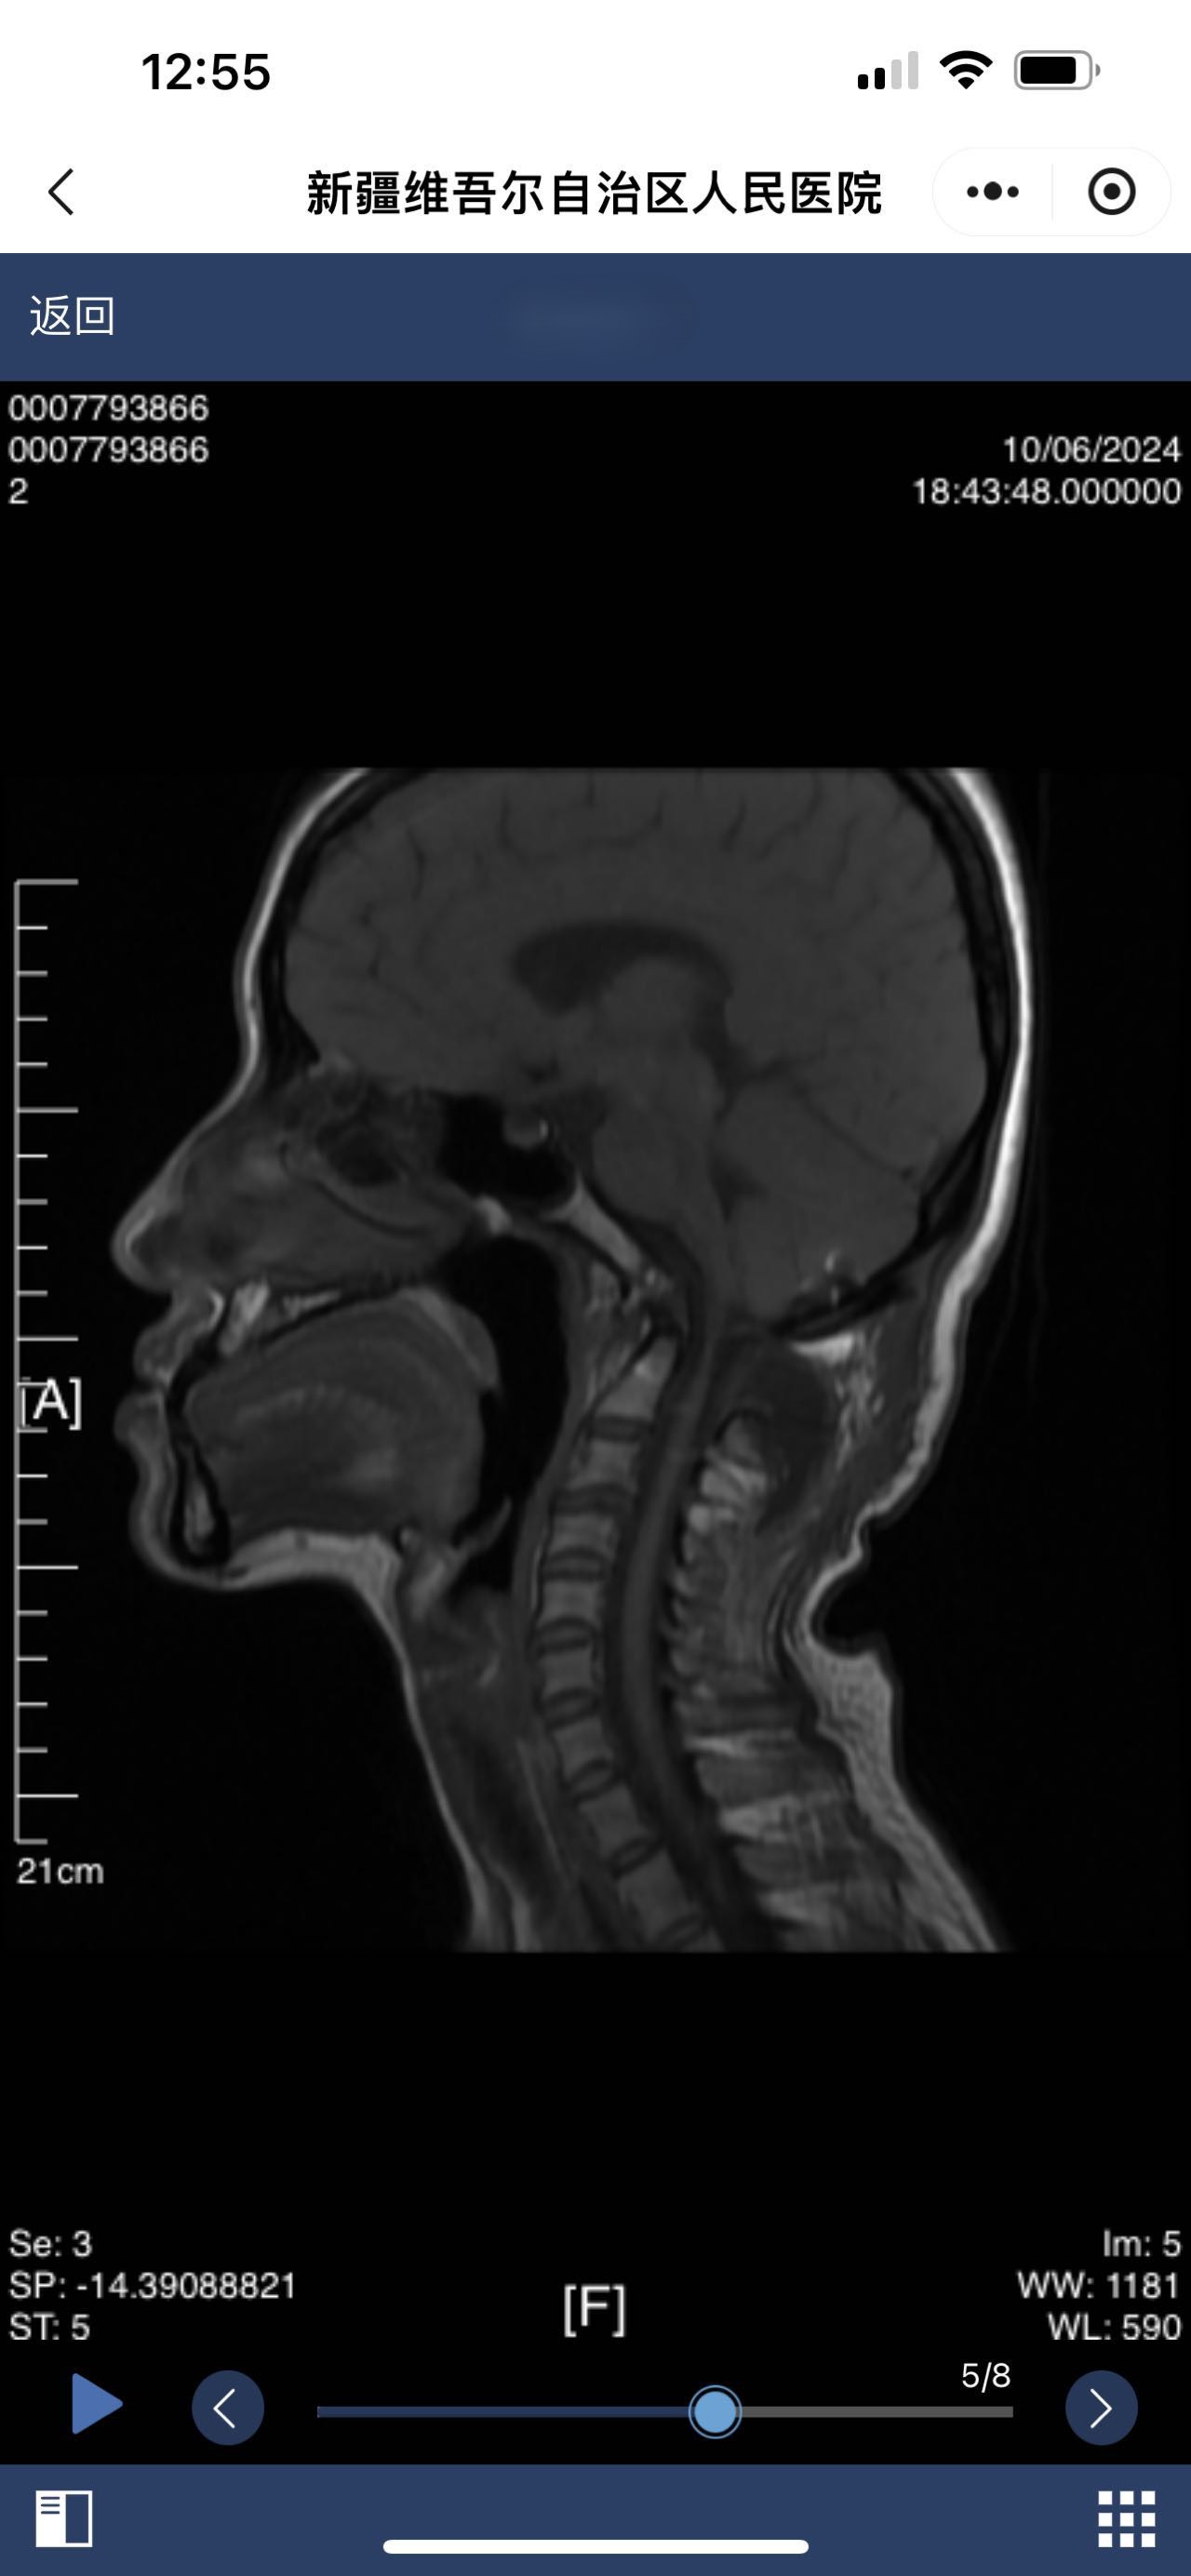

• 术后状况:术后颈后有积液

• 术后影像:

• 2024.10.06,积液范围略小。